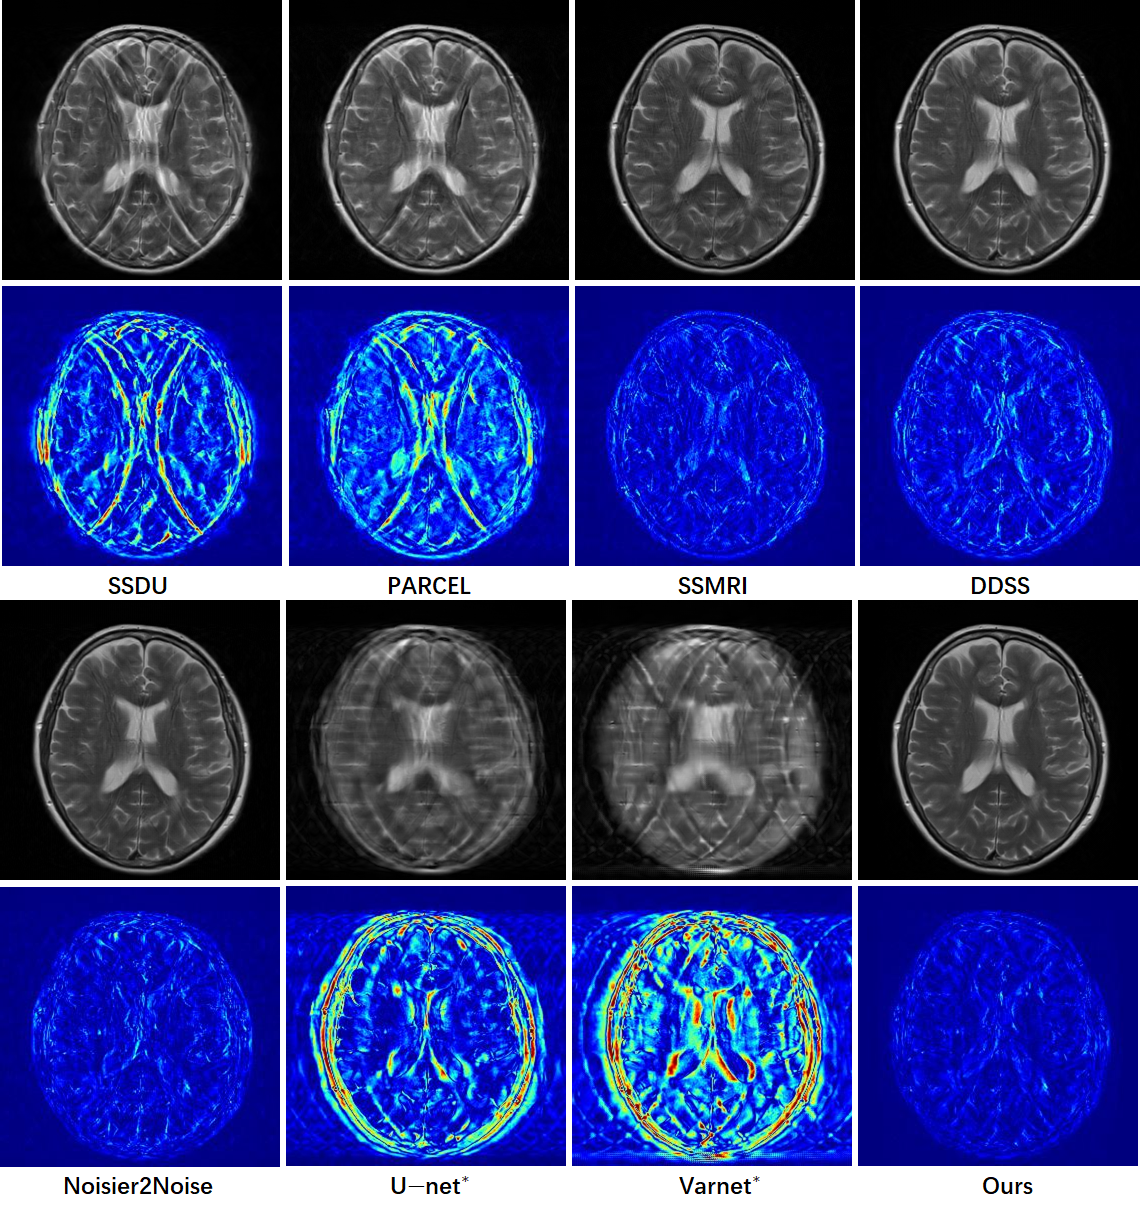

In Table 1, we present the quantitative comparisons in fastMRI dataset for T1- and T2-weighted image reconstructions under equispaced and random subsampling masks with 4× and 8× accelerations. The results demonstrate that our method achieves significant improvements in PSNR and SSIM compared to other self-supervised methods. Compared to supervised methods, our approach—powered by the advanced DUN-CP-PPA and a re-visible dual-domain self-supervised approach—outperforms the U-net supervised model, though there remains a performance gap when compared to the Varnet supervised model. Additionally, in Fig. 3, we provide a visual comparison of different approaches for T2-weighted images on the fastMRI dataset under equispaced subsampling with 4× acceleration. The second row highlights the zoomed-in region of interest (ROI), while the third row displays the corresponding error maps. From the close-up ROI and error maps, it is evident that our method achieves superior visual quality among all self-supervised methods, particularly for fine-grained structures, as indicated by the yellow and blue arrows.